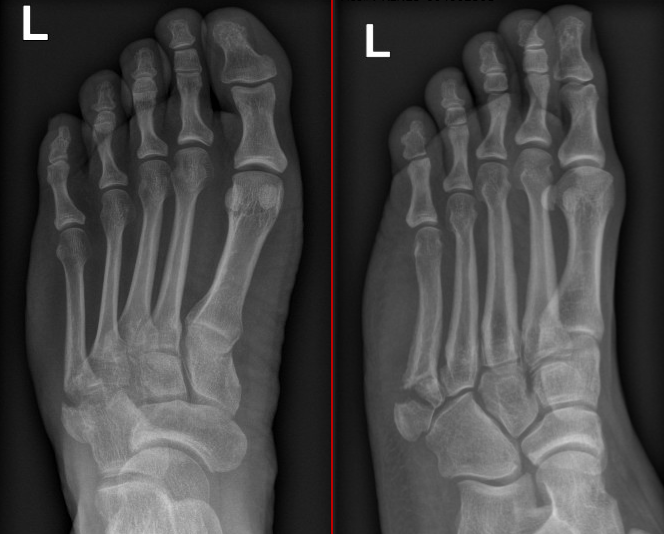

Figure 1: Multiple metatarsal fractures

Figure 2: CT demonstrates significant malalignment